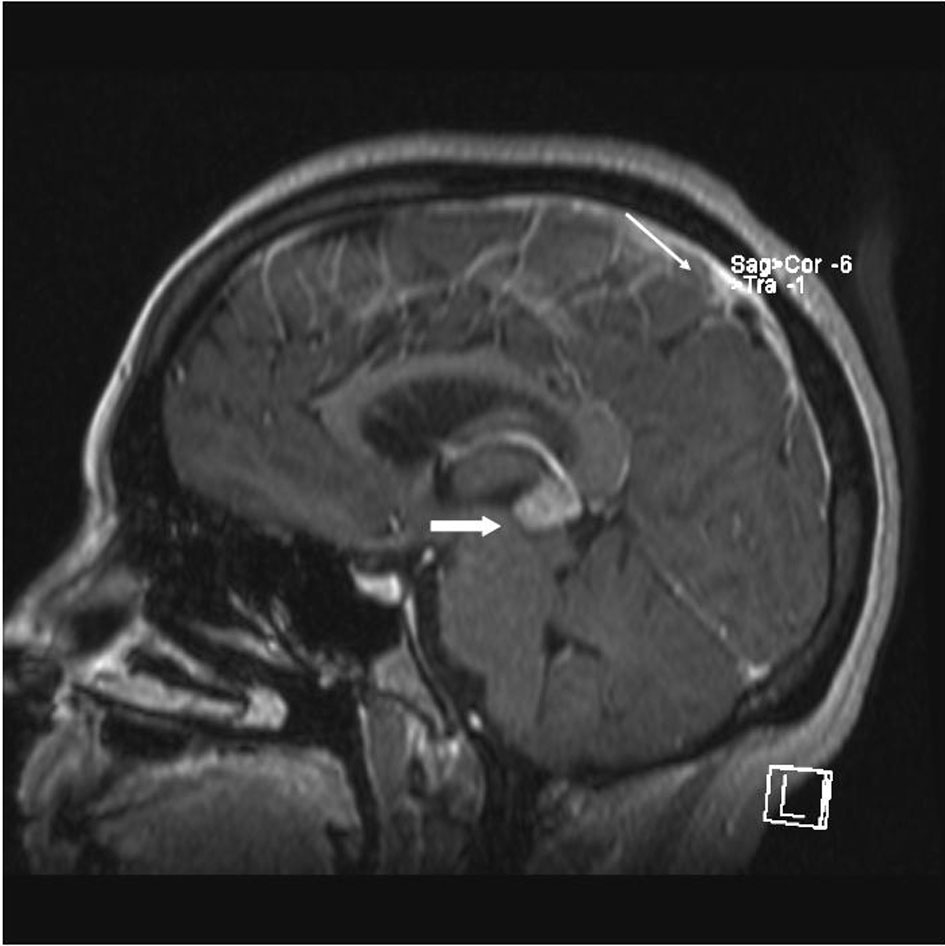

A 33 year old woman presented to the Emergency Department with bifrontal headaches and blurry vision. Her past medical history was significant for Crohn’s disease which required a subtotal colectomy; she was not on any medications at presentation. Physical examination was without additional abnormalities. Magnetic resonance imaging (MRI) of the head revealed an enhancing pineal gland mass (Fig.1 and 2, large arrow) and obstructive hydrocephalus. These findings were concerning for either a primary or secondary brain malignancy. Cerebral spinal fluid (CSF) examination revealed malignant cells from an unknown primary.

![]() Click for large image | Figure 1. MRI brain (saggital) reveals obstructive hydrocephalus caused by an enhancing pineal gland mass (large arrow) and leptomeningeal carcinomatosis (LC) (small arrow). |

The patient was admitted, and a ventriculostomy was placed to treat the hydrocephalus. When the patient stabilized, she received whole brain external beam radiation (3000 cGy in 10 fractions), which resulted in improvement of her vision. MRI defined the pineal gland metastasis and LC as the cause for the hydrocephalus (Fig. 1 and 2, small arrow). The LC progressed despite radiation necessitating the conversion of the ventriculostomy to a ventriculo-peritoneal shunt for the persistent symptomatic hydrocephalus.